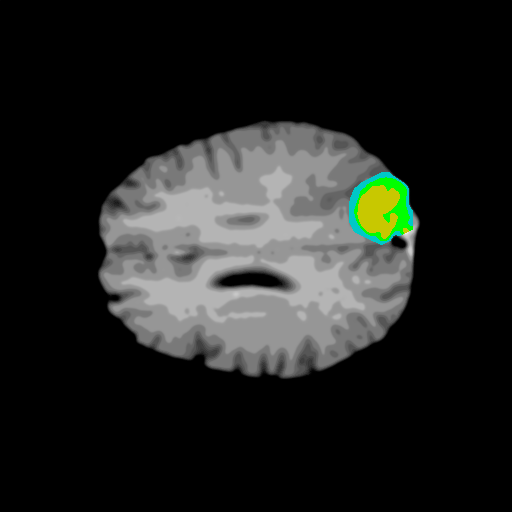

Extensive experiments have been performed in the current setup, and experimental outcomes are reported with the demonstration of numerical and statistical analyses using the proposed QFS-Net, QIS-Net [39], convolutional U-Net [18] and Residual U-Net (URes-Net) architectures [20]. The human expert segmented skull-tripped contrast enhanced DSC brain MR input image slices of size and ROIs are provided in Figure 5 as samples. The demonstration of QFS-Net segmented images followed by the essential post-processed outcome on the slice no. for class level with four distinct activation schemes () are shown in Figure 6. It is evident from the experimental data provided in Table LABEL:tab1 that the proposed QFS-Net performs optimally for the -connected quantum fuzzy pixel information heterogeneity assisted activation () with and gray scale set in comparison with other thresholding schemes and gray scale sets under the four evaluation parameters () [44]. The segmented tumors obtained using the proposed self-supervised procedure under class transition levels with four different thresholding schemes , , and are demonstrated in Figures 7- 8 for the class boundary sets and [39], respectively. The segmented images using the remaining two class boundary sets ( and ) [39] are provided in the supplementary materials section. The segmented ROIs describing the whole tumor region after the masking procedure using QIS-Net, U-Net and URes-Net are also reported in Figure 9.